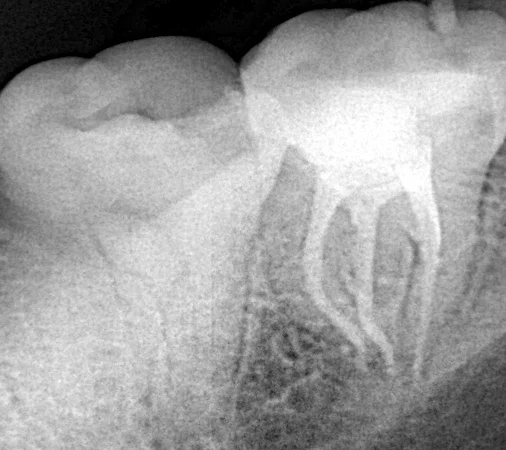

After Endodtontic treatment the tooth will be weak and brittle and bron to fracture more than the vital tooth with large loss in its stracture So when there is massive tooth stracture loss after Endodontic treatment we try to save…